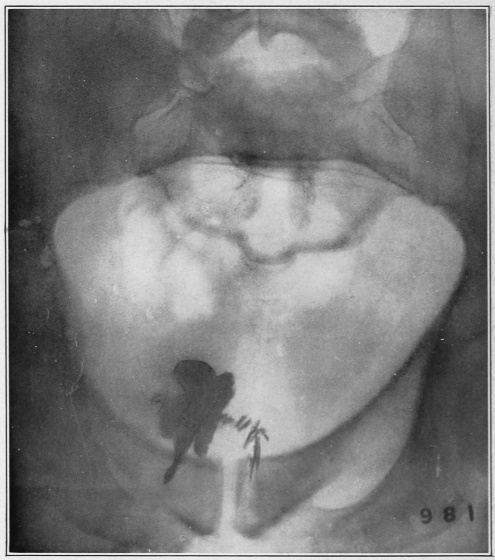

3 I found it more convenient to use the words mucus channel, mucus fistula, etc., in preference to sinus, as they better convey my ideas to the average reader.